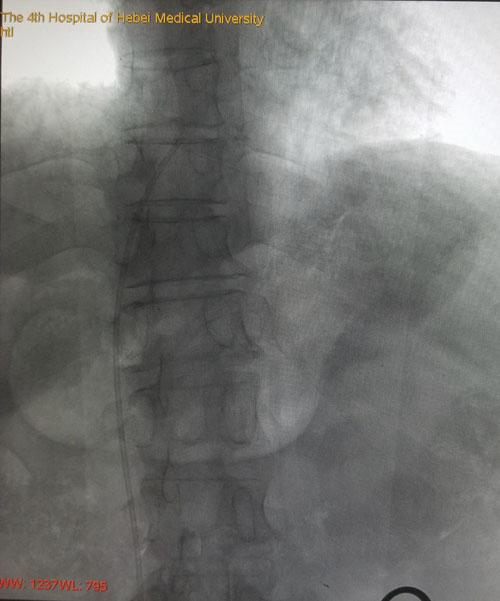

术后DSA评估导管尖端位置